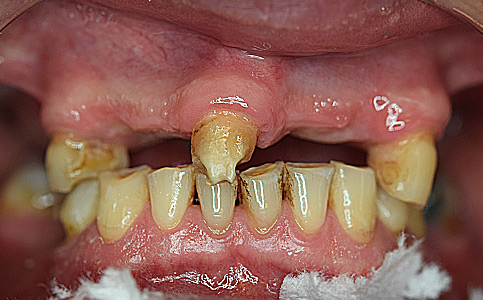

Pacjent zgłosił się do naszego Centrum stomatologii i Ortodoncji FRESHmed w Katowicach w celu poprawnia estetyki swojego uśmiechu. Po konsultacji i dokładnej diagnostyce, usunięto zęby dolne z powodu duzej ruchomości. Zęby zostały zastąpione 6 implantami zębowymi, na których odbudowano cały łuk zębowy dolny metodą All-on-6. Poprawę kształtu i koloru zębów górnych uzyskano poprzez zacementowanie koron pełnoceramicznych.